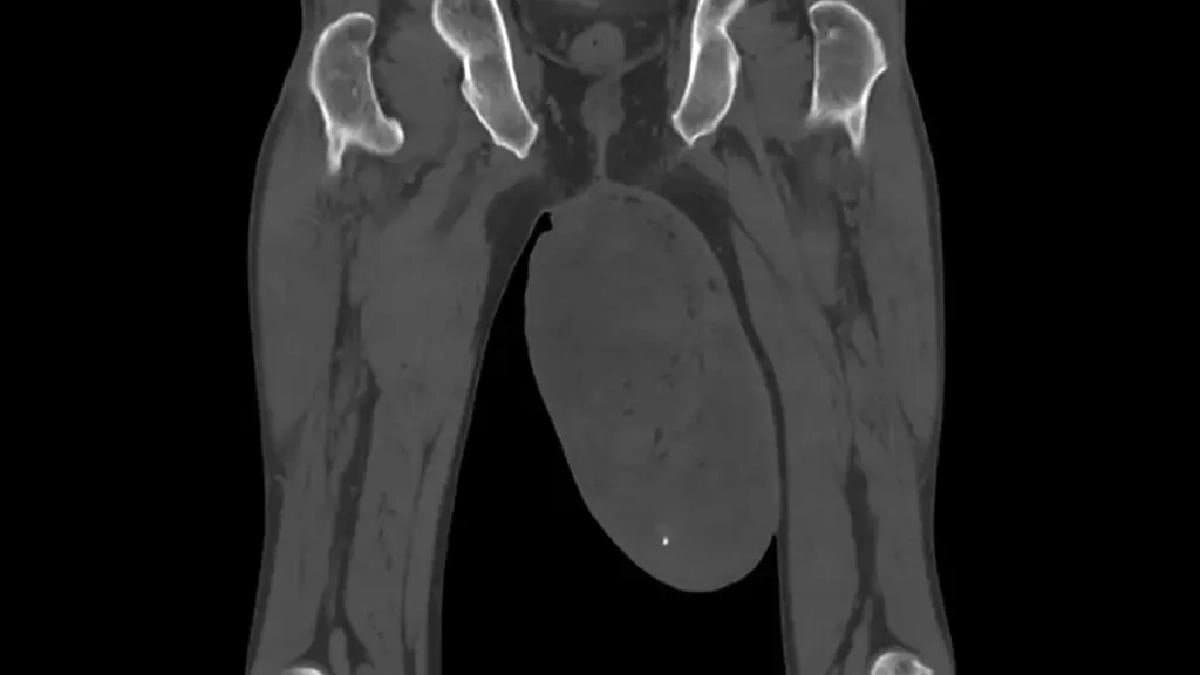

চিকিৎসক আরও জানান, পরীক্ষা করে দেখা যায় ওই ব্যক্তির অণ্ডকোষের আকার সাধারণ মানুষের তুলনায় প্রায় তিন থেকে চার গুণ বেশি বেড়ে গিয়েছিল। বাম অণ্ডকোষের দৈর্ঘ্য ছিল ৬.৬১ ইঞ্চি। প্রস্থ ৪.৮৪ ইঞ্চি। বাম অণ্ডকোষ ছাড়া রোগীর দেহে আর কোনও সমস্যা ছিল না। ছিলনা উচ্চ রক্তচাপ কিংবা ডায়াবেটিসের মতো কোনও সমস্যা। এমনকী তাঁর ডান দিকের অণ্ডকোষেও কোনও সমস্যা ছিল না। তেমনই দেখা যায় আলট্রা সাউন্ড পরীক্ষায়।

বিষয়টি পুরুষদের দেখে এতই বিরল যে এখনও পর্যন্ত চিকিৎসা বিজ্ঞানের ইতিহাসে মাত্র আটটি এমন রোগীর উল্লেখ আছে। নিজের কেস রিপোর্টে সেই বিষয় নিয়েও কথা বলেছেন চিকিৎসক। জানিয়েছেন পুরুষদের অণ্ডকোষে এই ধরনের টিউমারকে বলা হয় স্ক্রোটাল এএমএফ। এই ক্ষেত্রে রোগীর টিউমার ছিল মুরগির ডিমের মতো। উপগোলকের ন্যায়। চীনের এই রোগীর ক্ষেত্রে টিউমারটি আয়তনের দিক থেকে মধ্যম। ঠিকমতো চিকিৎসা না হলে টিউমারের দৈর্ঘ্য এক ফুটের বেশি হয়ে যেতে পারে।